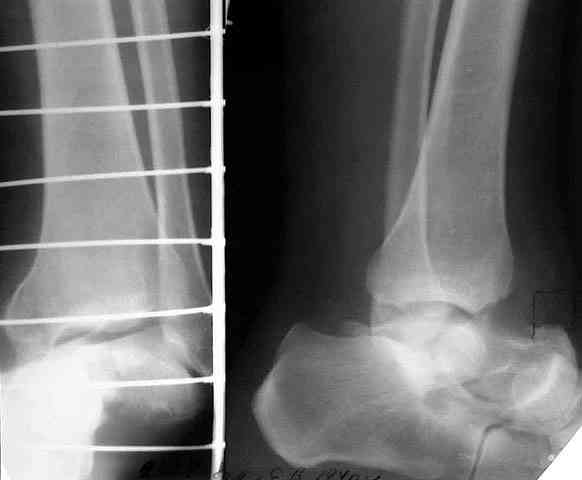

Не адресована другая проблемы - берцово-пяточный блок достигается ценой укорочения конечности на 3-4 см. Поэтому надо предусмотреть что-то для удлинения. У нас в клинике традиционный подход - билокально удлинять большеберцовую кость. Раньше еще и малоберцовую рубили на двух уровнях. Сейчас (спасибо коллегам из форума) пользуемся только

той остеотомией, которая делается для отворачивания кожно-костного лоскута с малоберцовой костью. Фиксируем все это аппаратом (пример в приложении) около 4 мес.

То есть относительно недолго. Про винты поэтому стоит вспомнить, только если опору со стопы хочется снять совсем уж рано. Можно, в принципе, и о штифтовании подумать. Правда, мы пока думаем - они так срастись успевают.